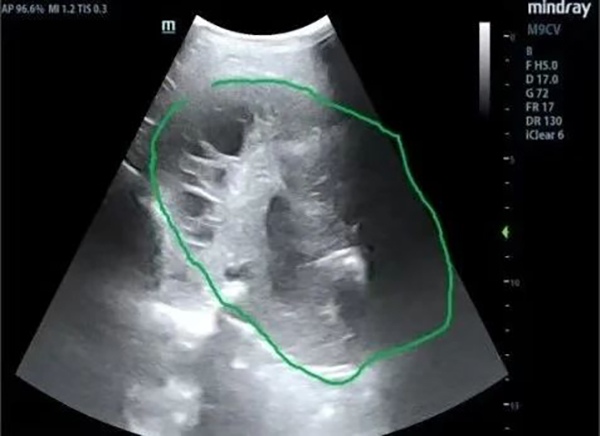

近日,一位70岁男性患者,因“反复咳喘3余年,加重1周”住院治疗。患者入院后行胸部CT提示右侧大量胸腔积液,进一步完善胸腔彩超提示:右侧包裹性胸腔积液。患者胸闷、气短症状明显,偶有痰中带血情况。抗感染治疗效果不佳。

为进一步明确诊断、改善患者症状,拟行包裹性积液胸腔穿刺置管引流术。但常规胸腔穿刺引流极易造成穿刺损伤及穿刺失败风险,较以往相比因技术难度和风险高。史淑利医生与青南支医专家范得艳医生综合分析患者病情后,决定联合超声科为患者行床旁超声引导下包裹性胸腔积液穿刺置管引流术。在手术过程中,由超声科医生首先对包裹性积液进行定位,由史淑利医生亲自为患者进行胸腔积液穿刺置管术,手术顺利完成。整个过程如同一场精细的外科手术,每一个步骤都严谨而准确。术后史淑利医生向年轻医生进行了胸腔穿刺术和胸腔积液的教学查房,向她们讲解胸腔穿刺的适应症、禁忌症、注意事项、可能出现的不良反应及处置方案,胸腔积液鉴别诊断。通过胸水结果分析,患者明确诊断“肺结核;结核性胸膜炎”,为患者制定了正规的抗结核治疗及随访方案。患者胸闷、气短症状得以缓解,患者及家属对治疗效果非常满意,对我院医护人员的专业技术和精心护理给予了高度赞扬。